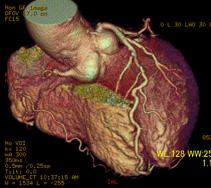

正常冠動脈